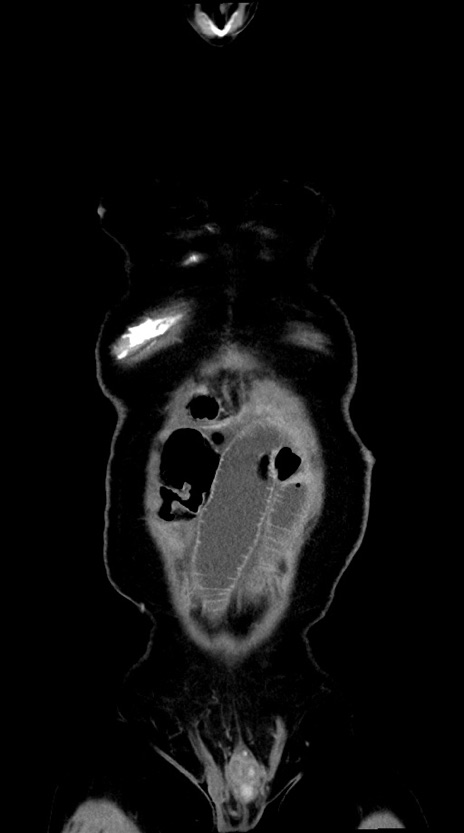

【症例】60歳代男性

【主訴】嘔吐

【現病歴】胃癌にて胃全摘後。食思不振が悪化し、夜中に嘔吐することがある。

【既往歴】胃癌、胃全摘、脾摘、胆摘後

【データ】WBC 5900、CRP 10.56